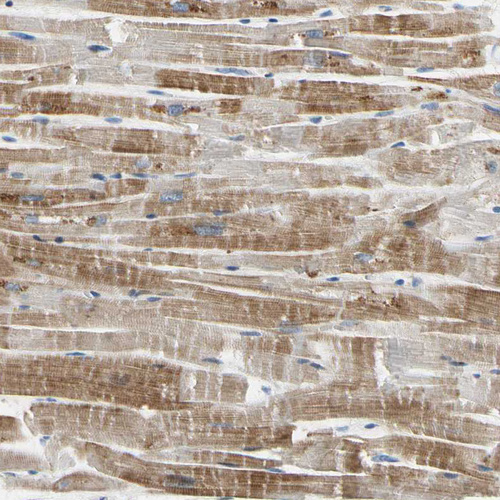

Immunohistochemical staining of human skeletal muscle shows moderate cytoplasmic positivity in myocytes.